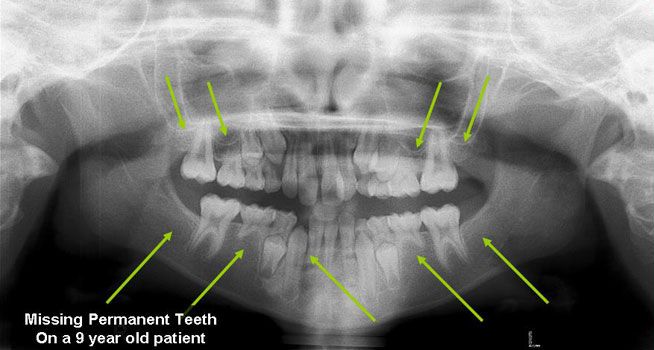

Missing Permanent Teeth

Hypodontia (the common dental term) describes a situation when fewer than 6 permanent teeth are missing, the term Oligodontia is used when more than 6 permanent teeth are missing (they were never formed). The most common missing teeth are the third molars (otherwise known as the Wisdom Teeth), followed by the premolars and the lateral incisors. Although it is not uncommon to have one missing tooth, patients with multiple missing teeth generally have a strong genetic component and it has been linked to conditions such as Ectodermal Dysplasia and several syndromes. Because early recognition aids in proper treatment, your dentist will refer you to specialists (orthodontist, oral surgeons, etc) that will determine which options suit you best to replace the missing teeth.